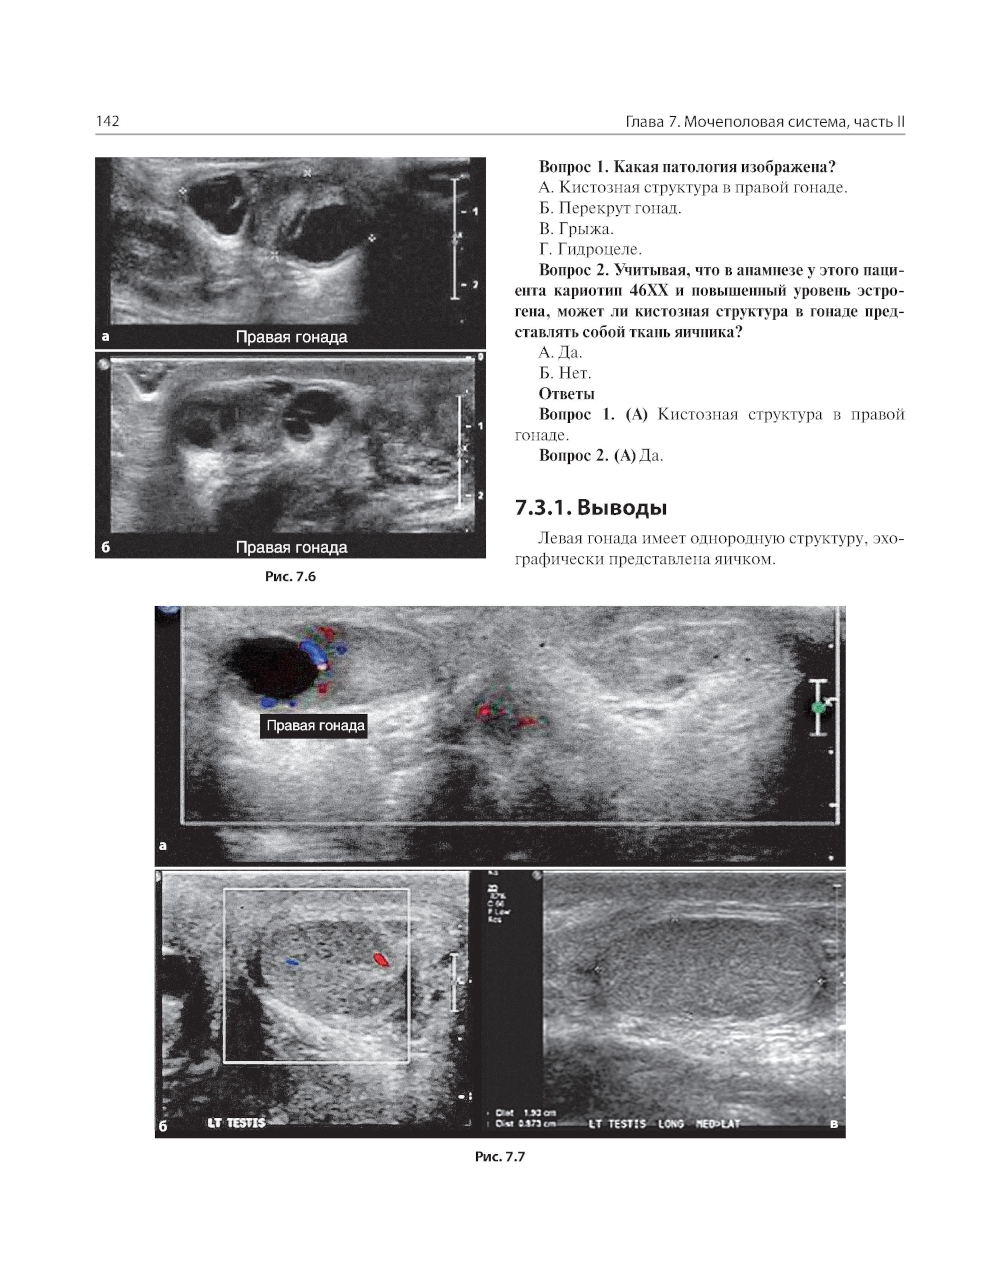

В книге рассмотрены сложные клинические радиологические случаи, охватывающие патологию центральной нервной системы, дыхательной и сердечно-сосудистой систем, желудочно-кишечного тракта, мочеполовой системы и опорно-двигательного аппарата в педиатрической практике. Случаи представлены с соответствующей историей болезни и подходящими изображениями исследований, за которыми следует обсуждение рентгенологических заключений при использовании различных методов лучевой диагностики. Также, в конце описания каждого случая выделены ключевые моменты, которые необходимо запомнить. Книга объединяет опыт врачей-рентгенологов и клинических ординаторов и представляет актуальную учебную информацию, способствующую улучшению качества оказания медицинской помощи. Издание предназначено врачам лучевой диагностики, врачам-радиологам и врачам клинической практики, работающим в педиатрических клиниках и детских больницах.| Издательство | ГЭОТАР-Медиа |